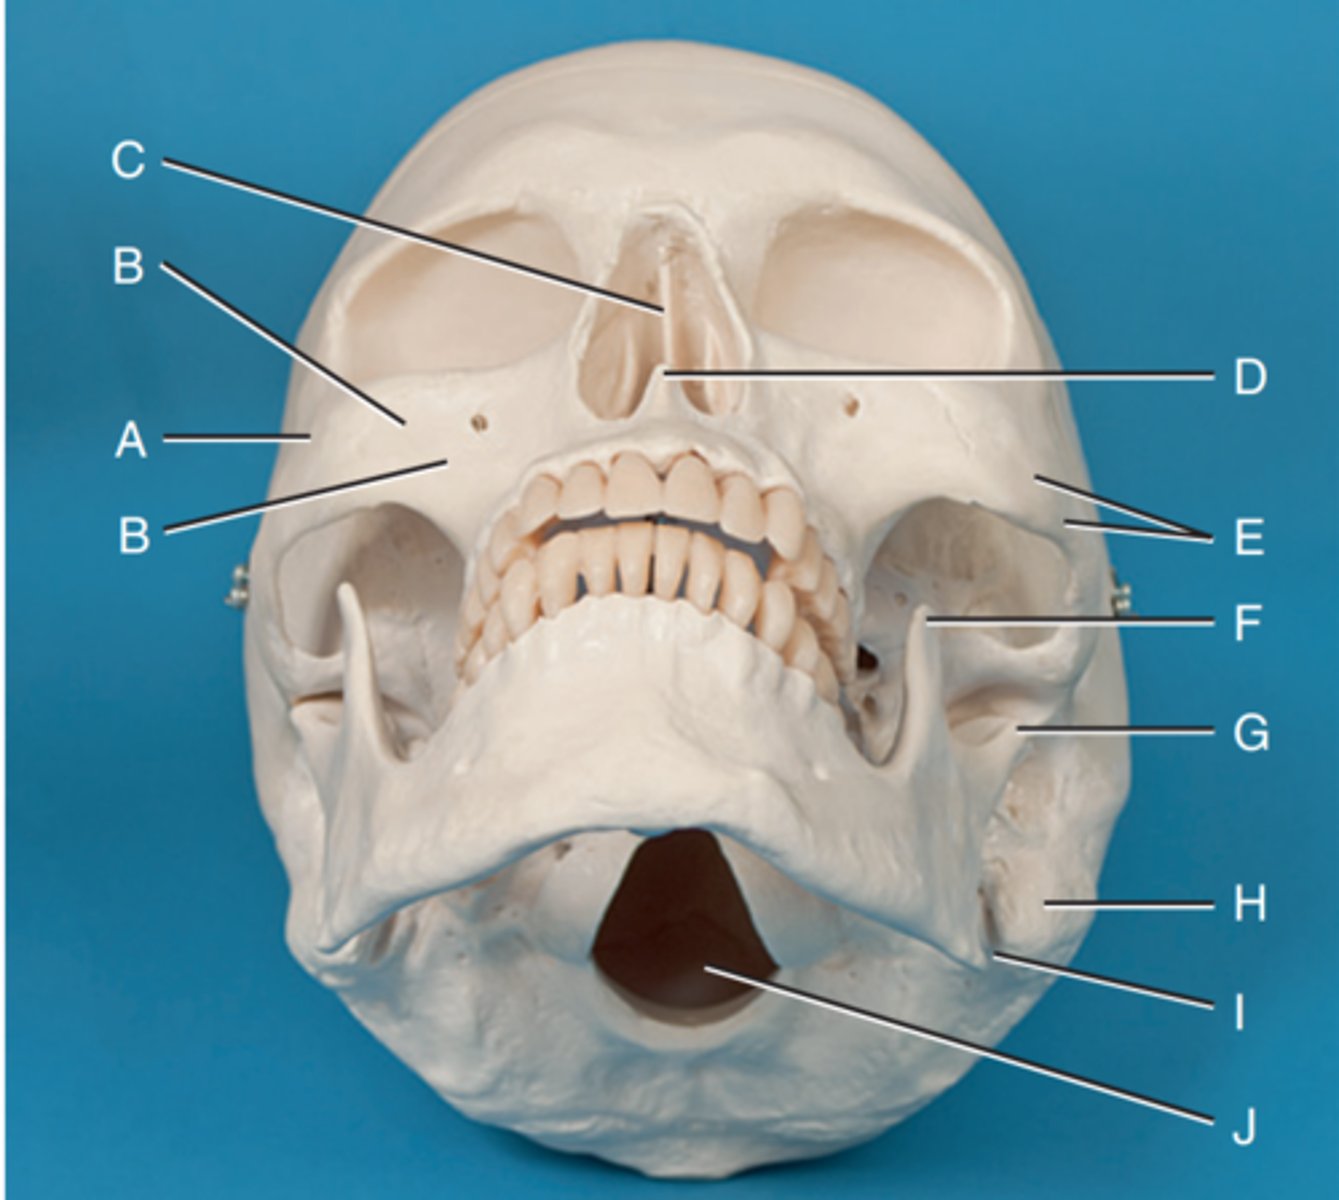

Zygomatic prominence

Label A

Body of maxilla

Label B

Bony nasal septum

Label C

Anterior nasal spine

Label D

Zygomatic arch

Label E

Coronoid process

Label F

Condyle

Label G

Mastoid process of temporal bone

Label H

Angle of mandible

Label I

Foramen magnum

Label J